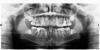

gambeat Опубликовано 28 мая, 2010 Поделиться Опубликовано 28 мая, 2010 (изменено) Добрый день, как видно в приложенном файле у меня достаточно своеобразные 8-ки, верхние и правую нижнюю мне уже удалили, но сегодня ортодонт сказала, что левую восьмерку можно не удалять, хотелось бы уточнить чем в будущем грозит неудаление левой восьмерки? Может ли возникнуть ситуация, что мне придется удалять нижнюю восьмерку в период ношения брекетов и чем это грозит? Заранее спасибо за ответ. P/S в названии темы опечатался, вопрос про левую нижнюю восьмерку, написал правую)), наверное потому что до сих пор побавливает). Изменено 28 мая, 2010 пользователем gambeat Ссылка на комментарий